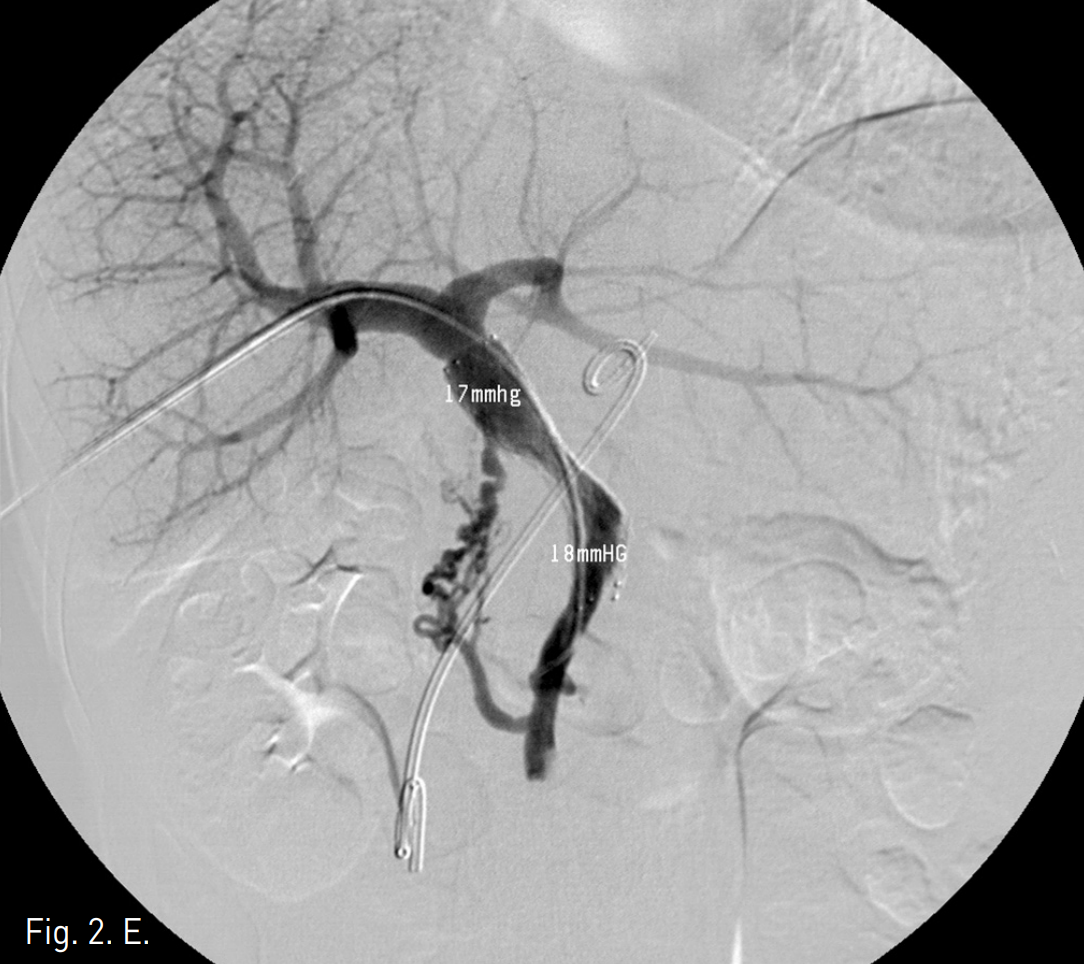

주문맥의 협착부위에서 10mm x 4cm balloon catheter (Synergy, Boston Scientific, Natick, Mass)를 사용하여 풍선확장술을 시행하였으나 elastic recoil로 인하여 반응이 없었음(Fig 2B-C). 자가팽창스텐트(14mm, 6cm, Zilver, Cook, USA)를 협착부위에 설치하고 10mm x 4cm balloon(Synergy, Boston Scientific, Natick, Mass)을 이용하여 post-stent balloon dilatation을 시행함. (Fig 2D)Stent 설치 후 협착 근위부와 원위부의 압력차는 1mmHg (SMV는 18mmHg, 주간문맥은 17mmHg)로 감소되었음(Fig 2E).

Fig. 2

E. After stent placement, portal stenosis is disappeared on portogram and pressure gradient between portal vein and SMV is decr eased to 1 mmHg. Also, visible collateral vessels are markedly decreased.